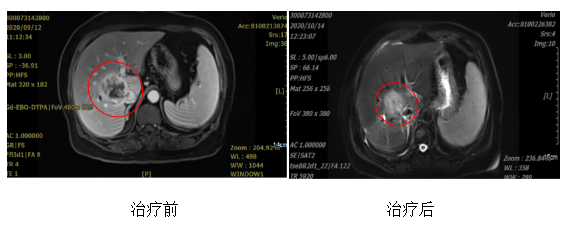

患者,女,76岁,肝胆管细胞癌,分期:cT1bN0M0 Ib期,Child-pugh分级:A级